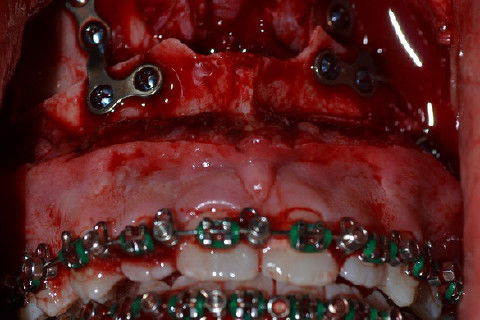

Fixação do avanço maxilar com placas de titânio do sistema 2.0

Fixação Maxilar

Fixação da Osteotomia Mandibular com 2 placas do sistema 2.0

Fixação da mentoplastia com 3 parafusos de 16mm do sistema 2.0 "Leg Scrow"